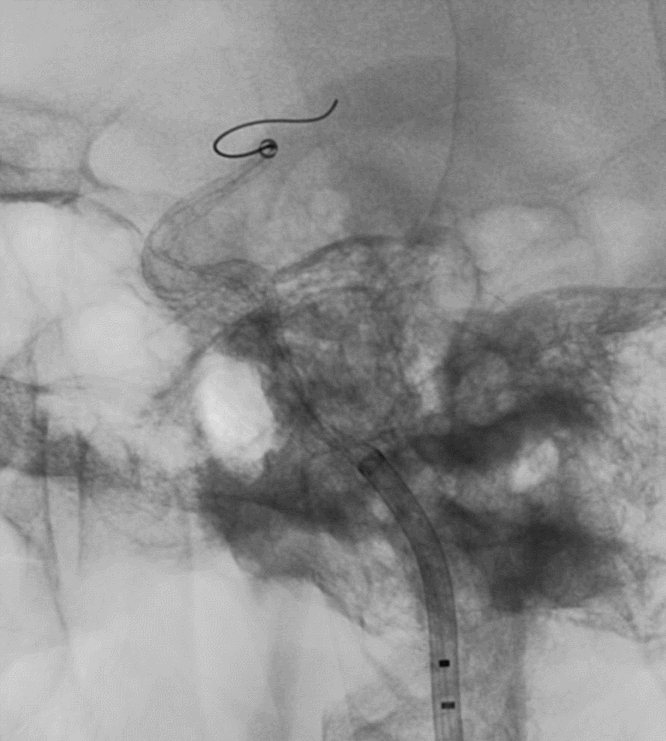

术后3月余复查:血管重塑良好,狭窄及动脉瘤均较前改善

术前                         术后3个月

左侧瘤体形态欠规则,4mm×30mm Streamline 优先处理左侧动脉瘤

术后3月复查,瘤体未见显影,载瘤动脉通畅

同期4mm×20mm Streamline 进一步处理右侧动脉瘤

术后4月余随访:多发动脉瘤均未见显影,远端残余轻度狭窄

术前术后对比